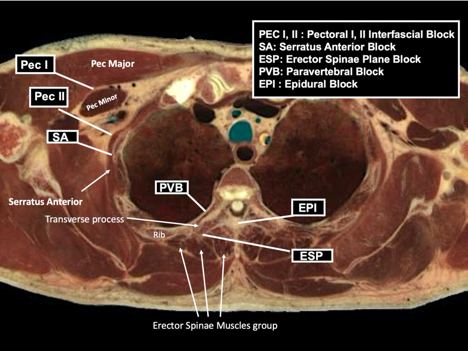

Table 1: Breast surgeries and their regional anesthesia implications

Table 2: Differences between regional anesthesia techniques for breast surgery